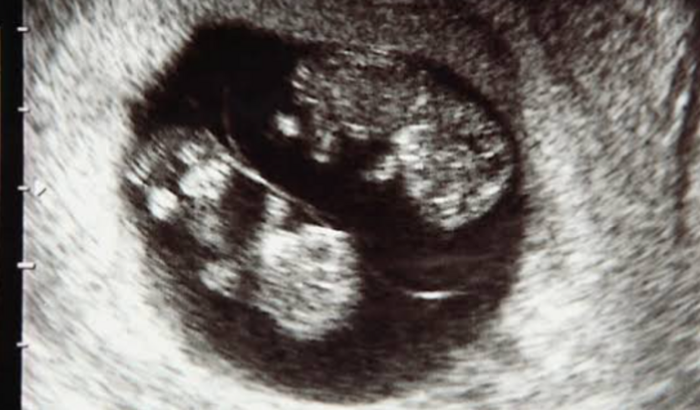

Olá sou André a irmã da minha esposa está esperando gêmeos e um deles está com uma obstrução na traqueia e devido a isso esta acumulando líquido, em decorrência disso os pulmões estão inchando e precionandono coração e precisa ser feita uma ressonância e o custo dela é entorno de 1600 a 1800 reais. No momento não posso pagar, pois se pudesse já teria resolvido. Peço àqueles que puderem contribuir de coração os bebês e a mãe agradece.